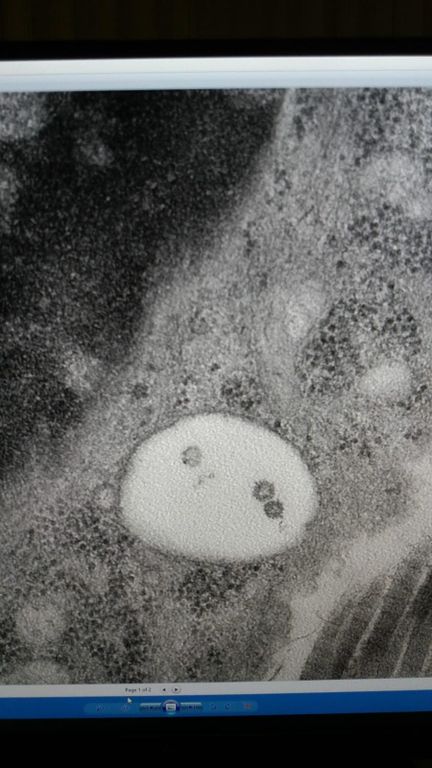

L’infezione da Covid19 si manifesta spesso con delle eruzioni cutanee che sembrano comuni malattie della pelle ma che talvolta assumono una morfologia anomala e del tutto peculiare. ll gruppo di dermatologia varesina in stretta sinergia con i patologi ha scoperto tra i primi al mondo insieme ad un gruppo di scienziati spagnoli, il virus annidato nella pelle. Addirittura due virus di specie diverse nella stessa cellula. (vedi foto all.ta). La scoperta è stata pubblicata sul prestigioso JEADV (Journal of the European Academy of Dermatology and Venereology)